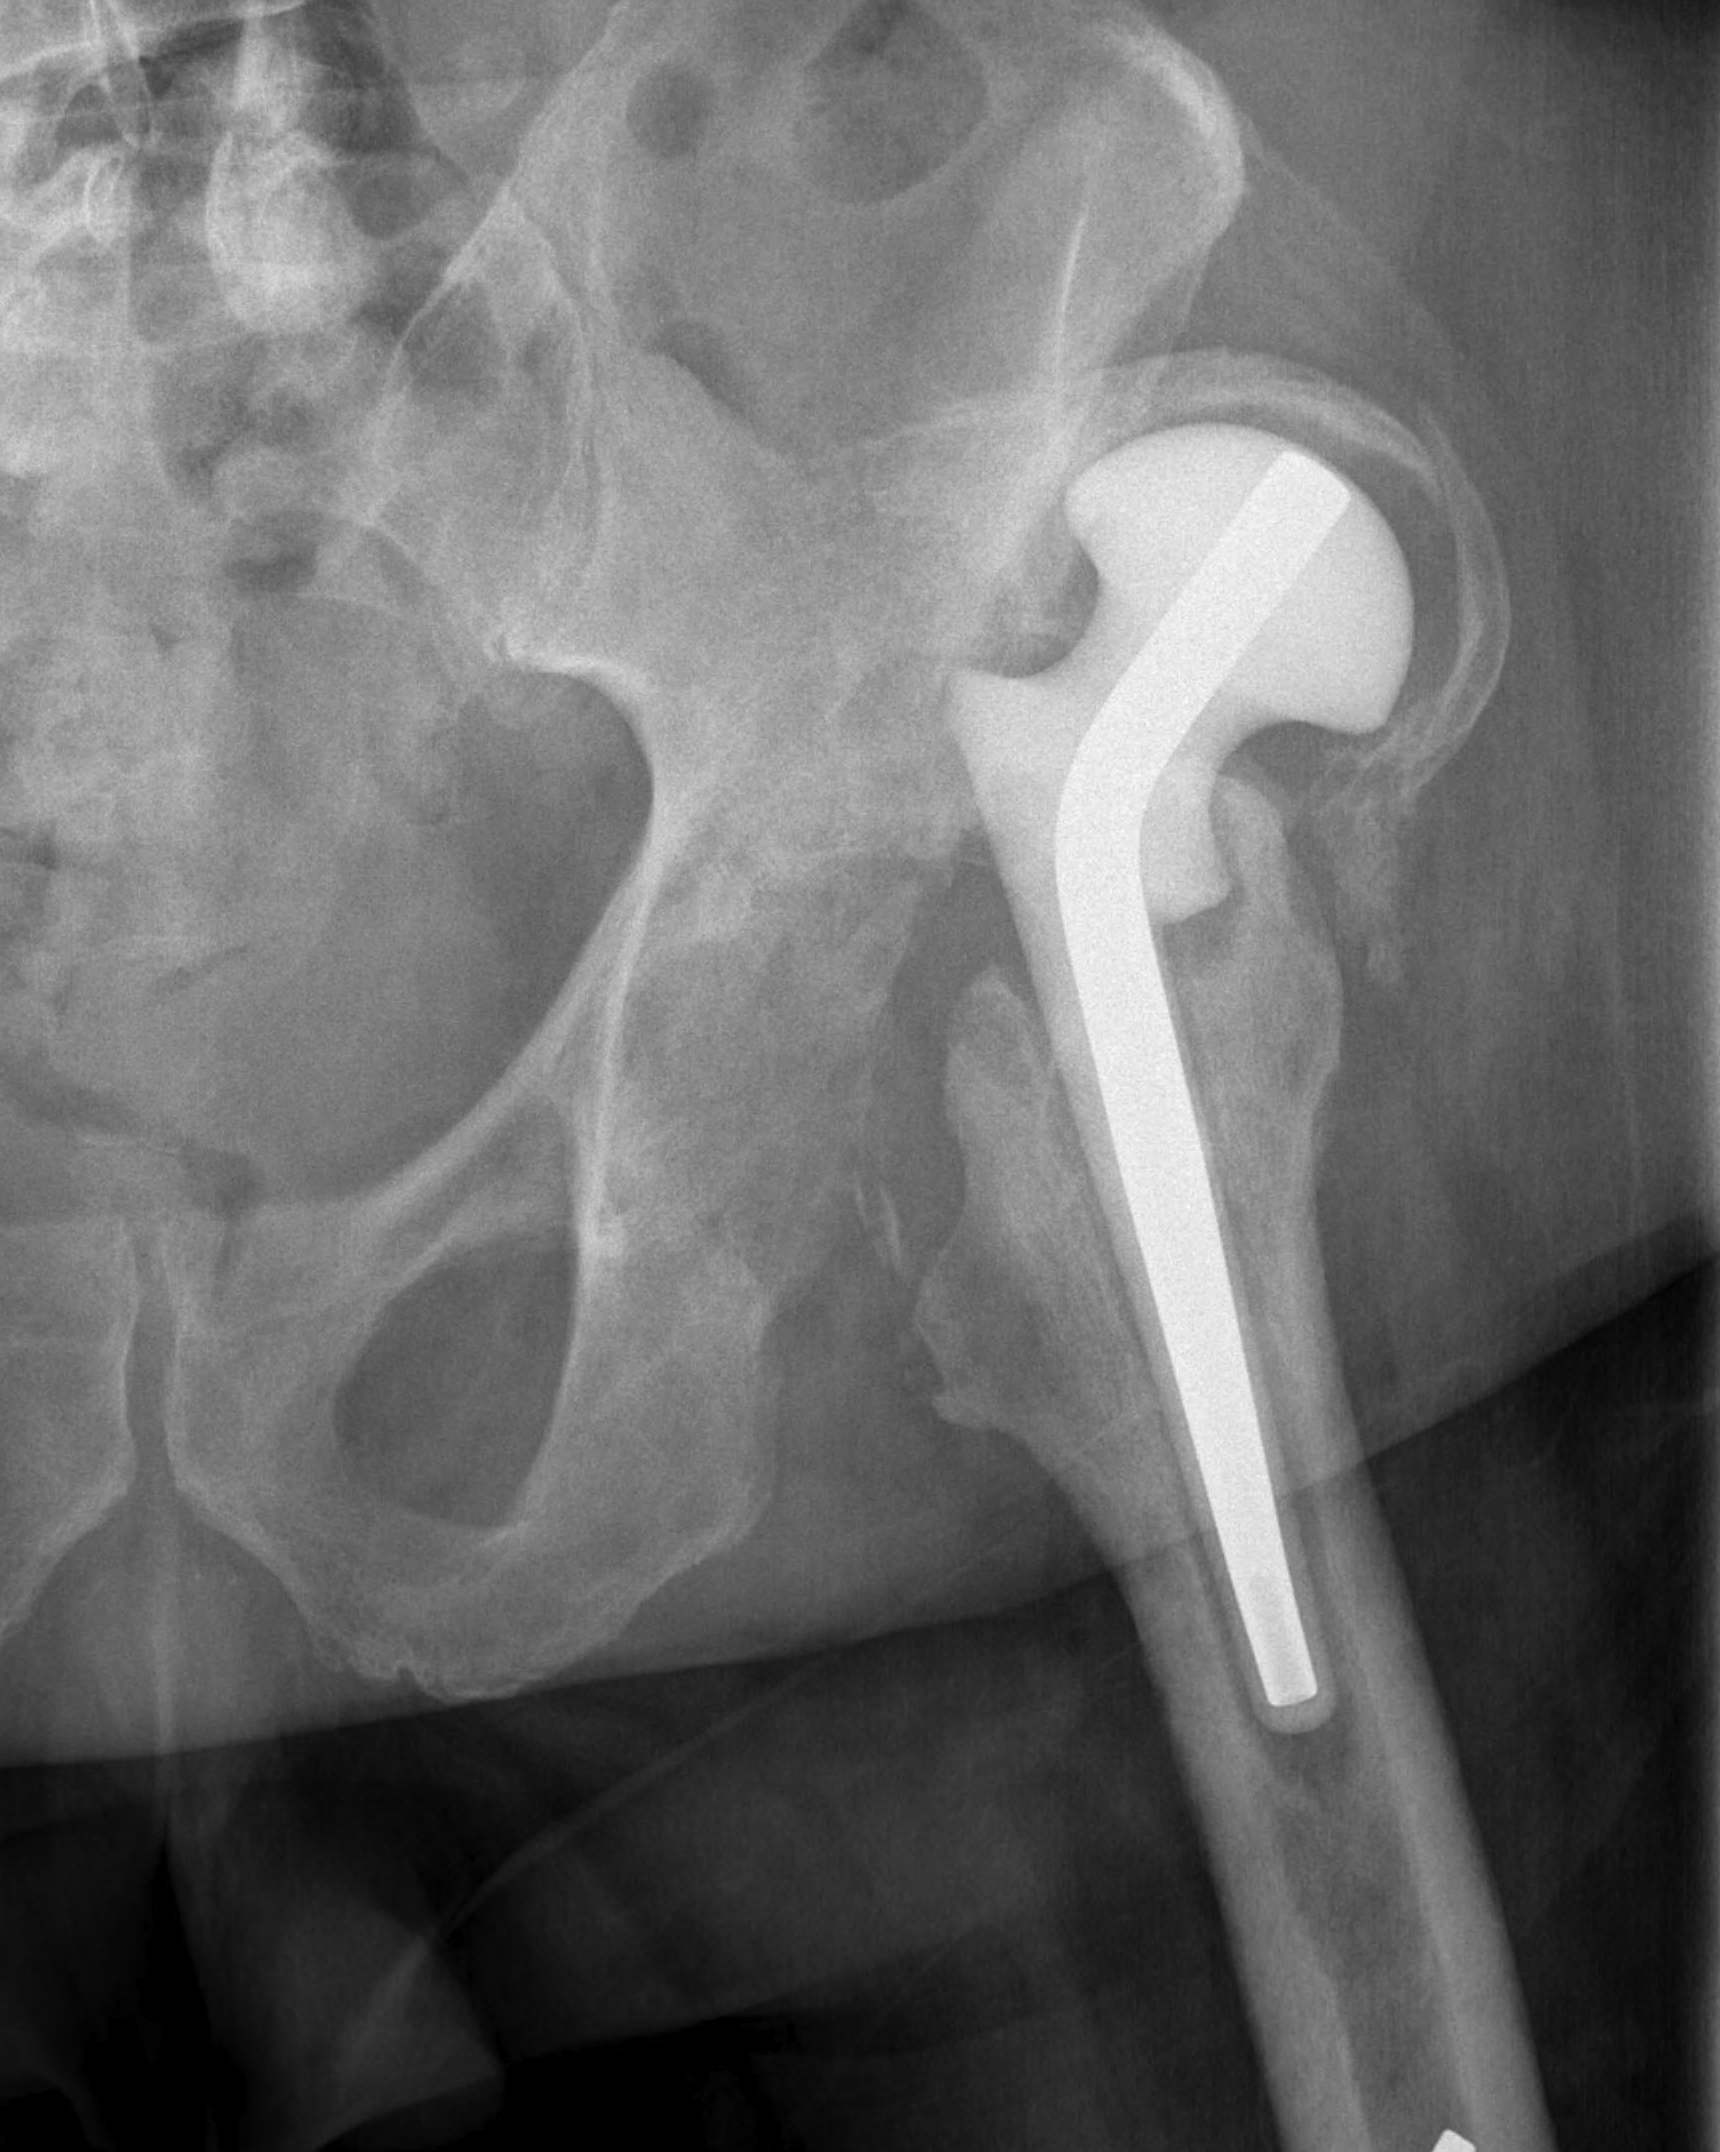

One-Stage Revision

Concept

Remove prosthesis, debride and replace at single sitting

- meticulous debridement critical

- antibiotic cement both femur and acetabulum

Technique

Debridement + removal of implants and all cement

- wash +++

- re-drape, new instruments

Implant cemented polished femur and all poly cup

- must use antibiotic cement

- guidance on antibiotic choice from multidisciplinary team (ID)

- for example add powder form vancomycin

- 2-3 gram vancomycin in each 40g packet of cement

Results

Lange et al Clin Epidemiol 2012

- systematic review of one- versus two-stage revision for hip PJI

- recurrent infection 13% one-stage

- recurrent infection 10% two-stage